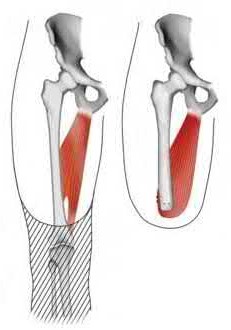

Figure A demonstrates a displaced subtrochanteric femur fracture with an intact lesser trochanter. The pull of iliopsoas on the lesser trochanter as well as the intact external rotators and gluteal musculature results in the the proximal fragment being in a flexed and externally rotated or abducted position (the most common post operative deformity). Reduction manuevers must be biologically friendly but also counteract the flexion/abduction moment. Lundy's review article discusses evaluation and treatment of subtrochanteric fractures. The review article details the various implants often used which include 95 degrees plates, femoral reconstruction nails, or trochanteric femoral nails with interlocking options. Lundy's article discourages the use of the 135 degree screw and side plate combo due to high failure rates in these fracture patterns. Bedi et al also review treatment of these fractures and discuss common

problems of malunion, nonunion, and implant failure. The article reviews reduction techniques that are soft tissue friendly, as well as the use of appropriate implants in these fracture types.